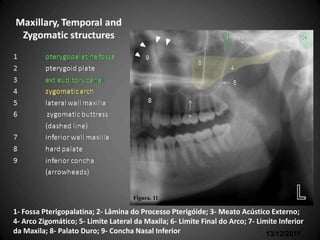

Partes Ósseas envolvidas com

seus respectivos nomes em inglês

Figura. 11

1- Fossa Pterigopalatina; 2- Lâmina do Processo Pterigóide; 3- Meato Acústico Externo;

4- Arco Zigomático; 5- Limite Lateral da Maxila; 6- Limite Final do Arco; 7- Limite Inferior

da Maxila; 8- Palato Duro; 9- Concha Nasal Inferior                             13/12/2011